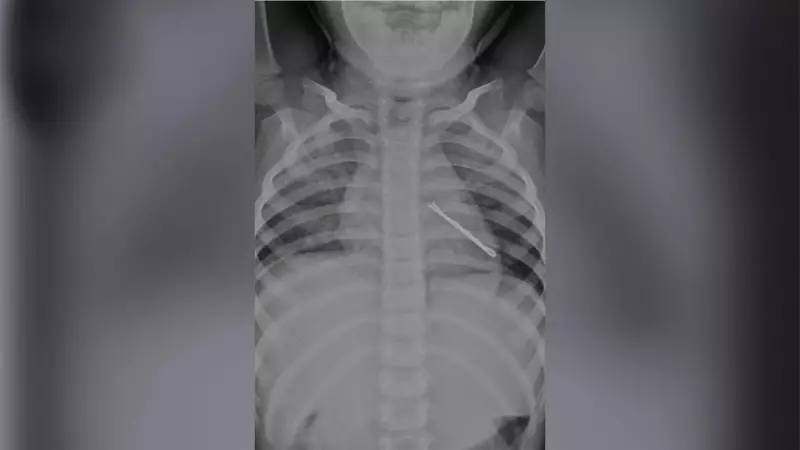

The young patient's ordeal began when she developed a persistent cough that lasted for two continuous weeks. Concerned parents sought medical help at multiple healthcare facilities, but the child showed no improvement despite routine medication. The breakthrough came when doctors at Jehangir Hospital conducted a thorough clinical evaluation and chest X-ray, which revealed the shocking truth - a metallic hairpin lodged in her left bronchus.

Following the successful extraction, the child's vital parameters remained stable, and her postoperative recovery was uneventful. The lung infection responded rapidly to treatment, and after a short course of antibiotics and nebulization therapy, the child showed significant improvement. A repeat chest X-ray confirmed the positive outcome, with resolution of respiratory symptoms and improved air entry on the left side.